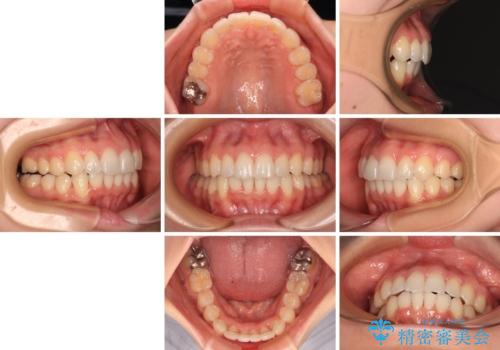

- 前歯のデコボコで前方に出ていることを気にして来院された患者様です。

上顎前歯が捻れて前方に飛び出しており、下顎前歯もそれに沿うようにデコボコとなっていました。

IPR(歯と歯の間を削る処置)によりスペースを獲得して上下顎前歯のデコボコを改善し、飛び出している前歯が引っ込むように設定し、インビザラインにて矯正治療を行うこととしました。

- 2年1ヶ月